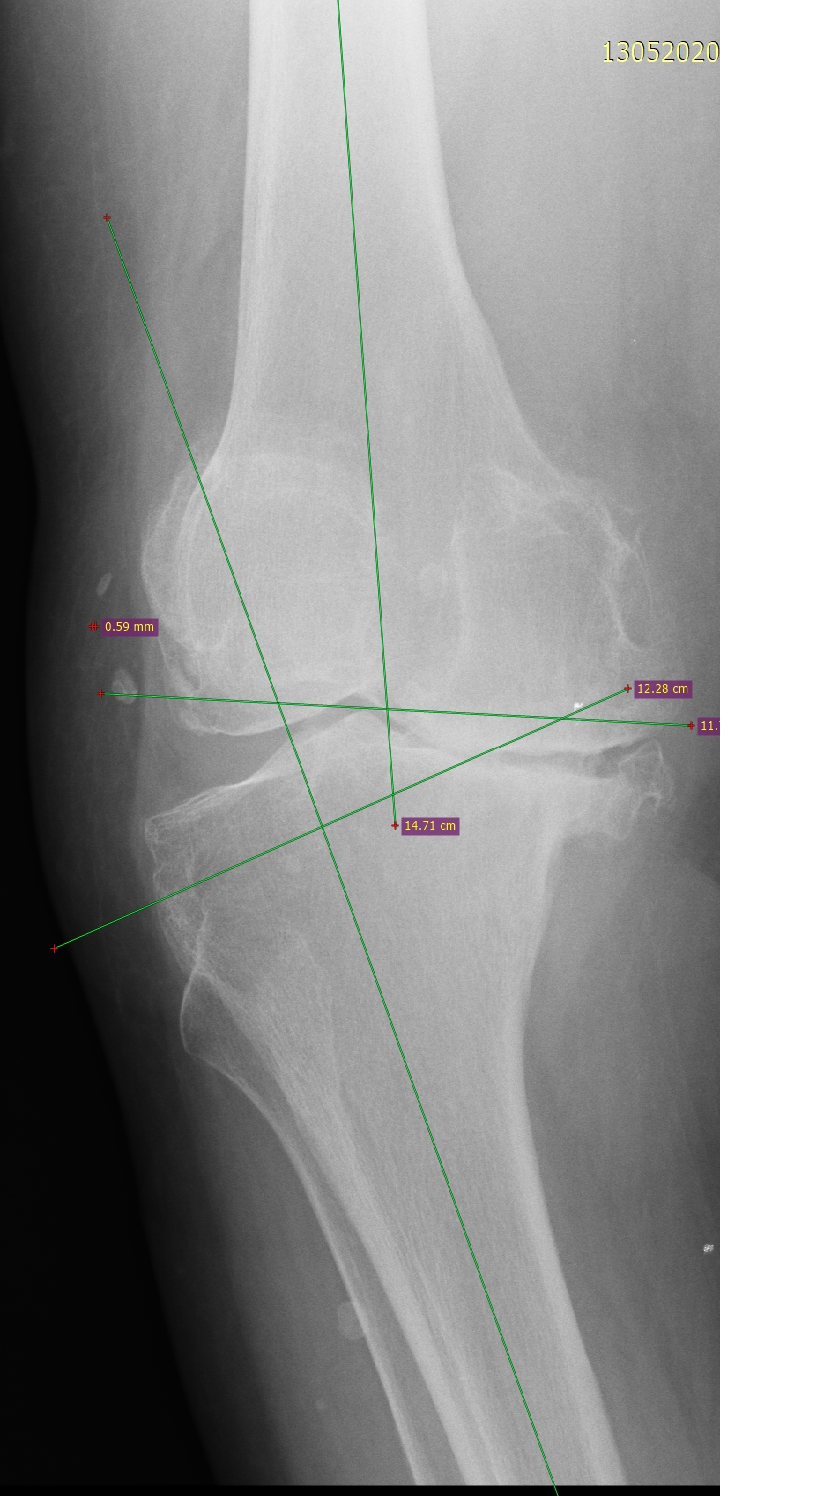

- Ендопротезиране на колянна и тазобедрена става

Основно лекувам заболявания на тазобедрена и колянна става чрез минимално инвазивно ендопротезиране, следтравматични и дегенеративни нарушения на ръката и китката и халукс валгус (популярен като „кокалчета на краката”).